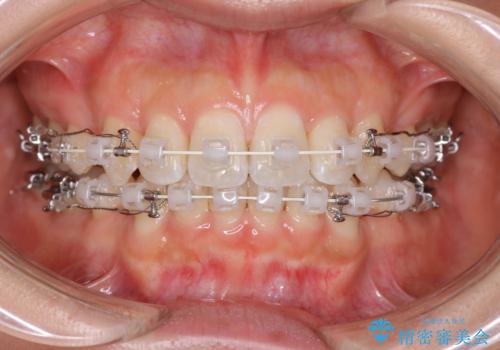

- 審美装置

- 口元をさげたいという主訴で来院されました。4番の歯を4本抜歯し、審美装置にて治療をしました。

抜歯をしたことで口元の突出感が改善しました。約2年を予定していた矯正ですが、約1年という短い期間で終了できました。